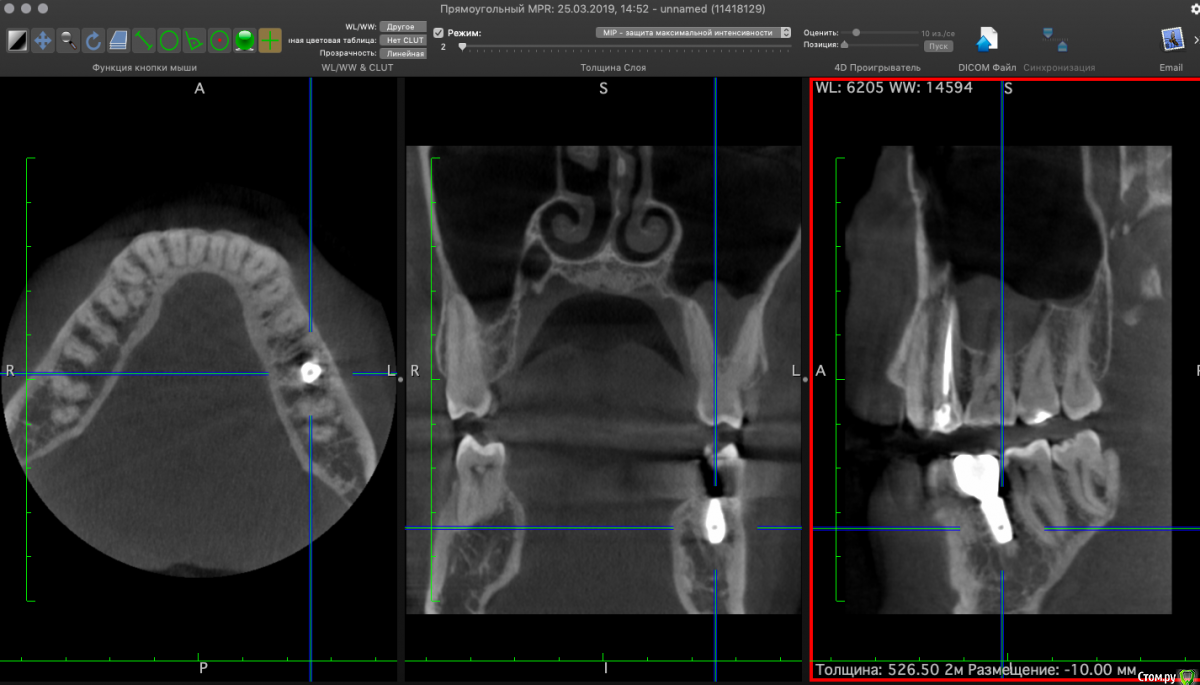

Nikitas Опубликовано 26 марта, 2019 Поделиться Опубликовано 26 марта, 2019 Восемь месяцев назад удален 36 зуб (на верхушках обоих корней был периодонтит), и одномоментно установлен имплантат. Полости, в которых было воспаление были заполнены графтом. На снимках КТ вокруг имплантата видны "полости", похоже что костной ткани в них нет. Уважаемые доктора, оцените пожалуйста, насколько такая степень приживления имплантата спустя 8 месяцев удачна, и каков прогноз? Будут ли эти полости зарастать костной тканью и насколько большая вероятность, что в них попадет инфекция? Насколько существенно, что имплантат установлен немного под наклоном? Субъективно жалоб нет. Ссылка на комментарий

Neilrus Опубликовано 26 марта, 2019 Поделиться Опубликовано 26 марта, 2019 чернота которую вы принимаете за пустоту - это шум от металла.Если вас ничего не беспокоит, то живите спокойно )наклон не беда. Ссылка на комментарий